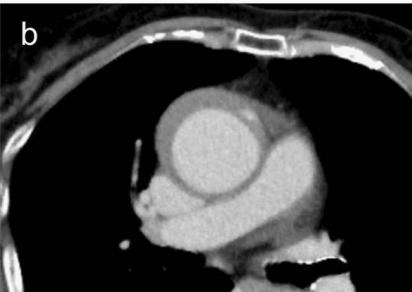

病例4

鲁迅说:孔乙己大约的确已经挂了!

下图的胸部CT平扫,基本上大约肯定可以看到一条线样阴影,将主动脉一分为二!

图10

增强CT一看,主动脉裂开了!

图11